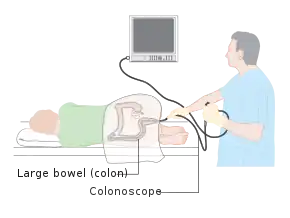

Colonoscopy is the endoscopic examination of the large bowel and the distal part of the small bowel with a CCD camera or a fiber optic camera on a flexible tube passed through the anus.[2]

The first step is usually a digital rectal examination, to examine the tone of the sphincter and to determine if preparation has been adequate. The endoscope is then passed through the anus up the rectum, the colon (sigmoid, descending, transverse and ascending colon, the cecum), and ultimately the terminal ileum. The endoscope has a movable tip and multiple channels for instrumentation, air, suction and light. The bowel is occasionally insufflated with air to maximize visibility (a procedure that gives the patient the false sensation of needing to take a bowel movement).[50] Biopsies are frequently taken for histology. Additionally in a procedure known as chromoendoscopy, a contrast-dye (such as indigo carmine) may be sprayed through the endoscope onto the bowel wall to help visualise any abnormalities in the mucosal morphology. A Cochrane review updated in 2016 found strong evidence that chromoscopy enhances the detection of cancerous tumours in the colon and rectum.[51]

In most experienced hands, the endoscope is advanced to the junction of where the colon and small bowel join up (cecum) in under 10 minutes in 95% of cases. Due to tight turns and redundancy in areas of the colon that are not "fixed", loops may form in which advancement of the endoscope creates a "bowing" effect that causes the tip to actually retract. These loops often result in discomfort due to stretching of the colon and its associated mesentery. Manoeuvres to "reduce" or remove the loop include pulling the endoscope backwards while twisting it. Alternatively, body position changes and abdominal support from external hand pressure can often "straighten" the endoscope to allow the scope to move forward. In a minority of patients, looping is often cited as a cause for an incomplete examination. Usage of alternative instruments leading to completion of the examination has been investigated, including use of pediatric colonoscope, push enteroscope and upper GI endoscope variants.[52]